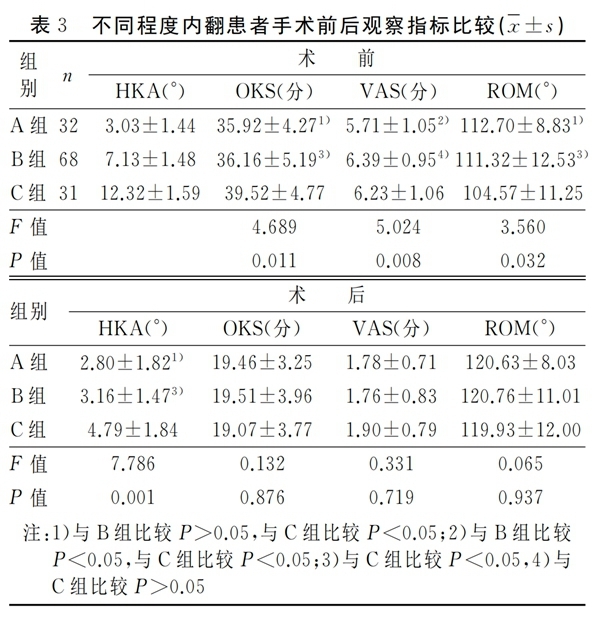

2.2 组间比较

三组患者的术前OKS、VAS及膝关节ROM比较差异有统计学意义(P<0.05)。组间两两比较,A组与B组的术前OKS和膝关节ROM比较差异无统计学意义(P>0.05),C组分别与A组、B组的术前OKS及膝关节ROM比较,差异有统计学意义(P<0.05);A组分别与B组、C组的术前VAS比较差异有统计学意义(P<0.05),B组与C组的术前VAS比较差异无统计学意义(P>0.05)。三组患者的术后HKA比较差异有统计学意义(P<0.05)。组间两两比较,A组与B组的术后HKA比较差异无统计学意义(P>0.05),C组分别与A组、B组比较差异有统计学意义(P<0.05)。三组患者末次随访时的OKS、VAS及膝关节ROM比较,差异无统计学意义(P>0.05),见表3。

膝关节骨关节炎患者往往伴有下肢力线不同程度的改变,并且绝大部分以内翻畸形为主,原因主要与膝关节内侧关节间隙相对于外侧间隙磨损变窄有关。关节的受力由下肢力线决定,内翻畸形将会导致内侧间室受力增加、骨关节炎病程的持续进展。有研究结果显示内翻程度的增加将会使患者骨关节炎的症状加重,在本研究中证实术前不同程度内翻组别的患者在OKS评分、VAS评分及膝关节ROM上存在显著差异,并且患者的术前OKS评分和膝关节ROM与下肢内翻程度呈现显著相关性。术前患者内翻畸形程度越大,膝关节功能则越差。术前下肢力线内翻畸形程度可以作为判断患者骨关节炎程度的重要指标。

3.2 术前下肢内翻畸形对术后力线的影响

对于UKA术后下肢力线的影响因素仍存在争议。Kim对124例活动平台UKA患者术后的下肢力线研究发现,UKA术后的下肢力线与胫骨和股骨的假体组件的位置无明显关系,术后下肢力线主要取决于聚乙烯衬垫的厚度。但Zhang等人回顾性分析了122例UKA的术后下肢力线得出,患者术后下肢力线与术前下肢力线的排列及术中截骨量有关,与垫片厚度无明显关系。Mullaji等认为UKA术后患肢的下肢力线将恢复到与未患骨关节炎的对侧肢体相当的水平。本研究结果表明,患者UKA术前下肢力线排列与术后下肢力线排列有显著相关性,术前下肢力线重度内翻组患者的术后下肢力线与术前轻度内翻畸形组及中度内翻畸形组间存在显著差异,术前下内翻畸形越大的患者,UKA术后下肢力线内翻度数也越大,术前下肢力线内翻畸形程度是影响术后下肢力线的重要因素。

如前所述,UKA术前膝关节内翻程度在一定程度上代表着骨关节炎的严重程度。本研究纳入的三组患者,在年龄、体重等方面差异无统计学意义,并且均由同一医师主刀,在UKA术后三组患者末次随访时的OKS评分、VAS评分、膝关节ROM并无显著差异,虽然术前重度内翻组患者术后内翻程度相对于轻度内翻组及中度内翻组较大,但术后下肢力线仍然保持轻度内翻的状态,符合UKA术后力线的最佳范围,术前不同程度的内翻畸形并未对UKA术后的短期临床疗效造成显著影响。